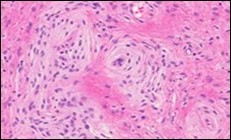

Figure 3.Soft tissue perineurioma with whorls and fascicles of neural cells displaying wavy nuclei, elongated cytoplasmic fibrils and intermingling of collagen fibres 13.